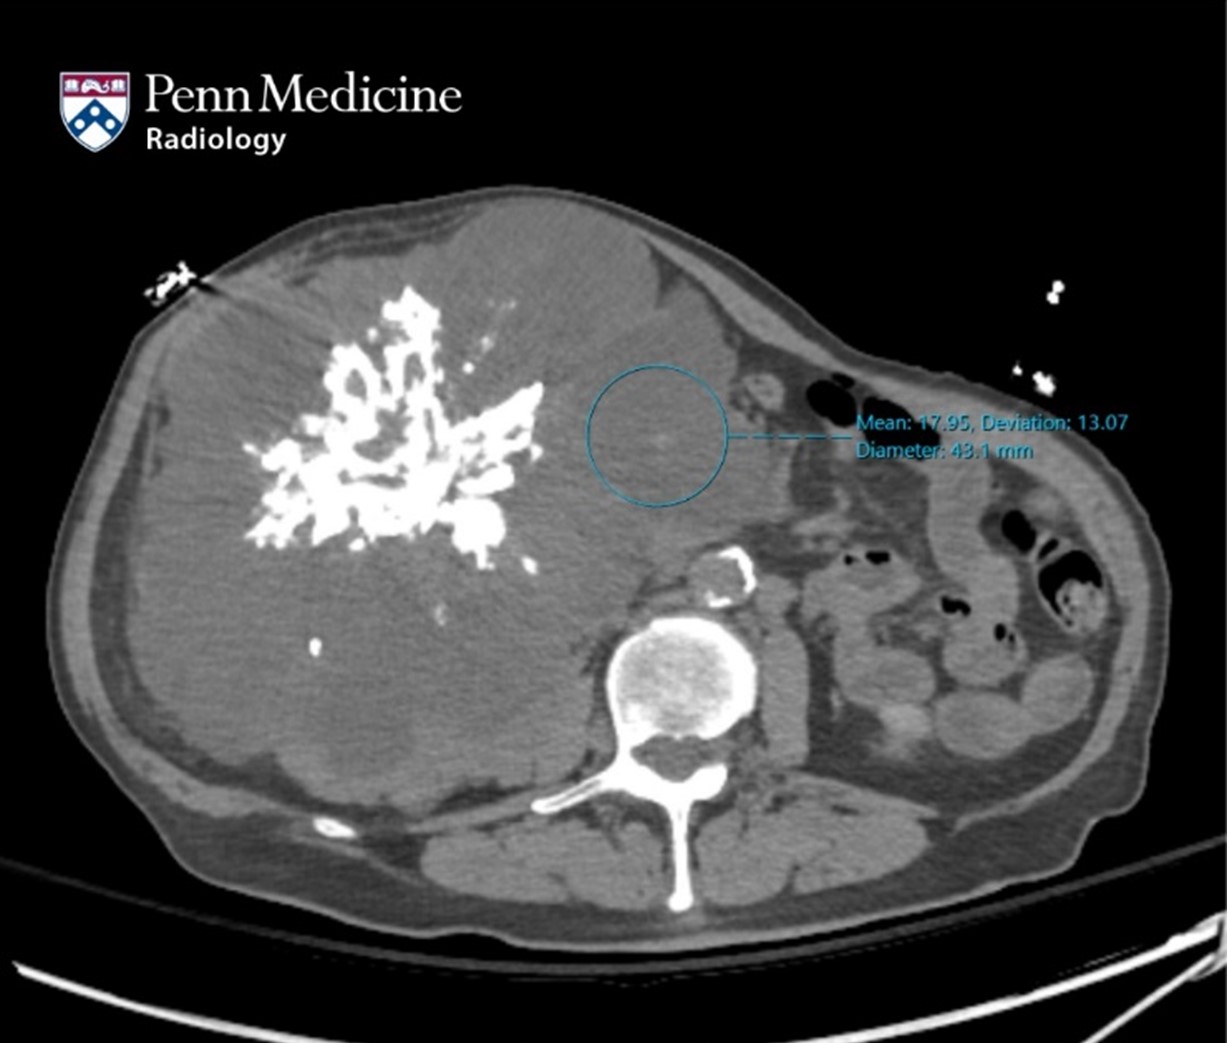

47-year-old man with growth on hepatic cyst

A 47-year-old man with Peutz-Jeghers syndrome (PJS) who had undergone sclerotherapy at another hospital for a cyst in hepatic segment IV presented wit…